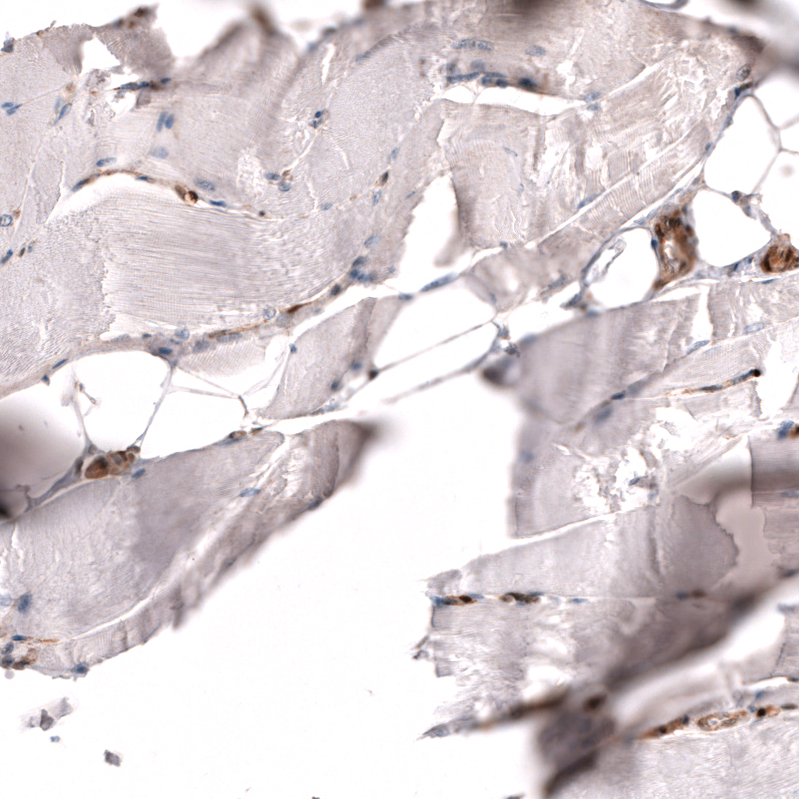

Immunohistochemistry analysis in human lymph node and skeletal muscle tissues using AMAb91735 antibody. Corresponding PTEN RNA-seq data are presented for the same tissues.